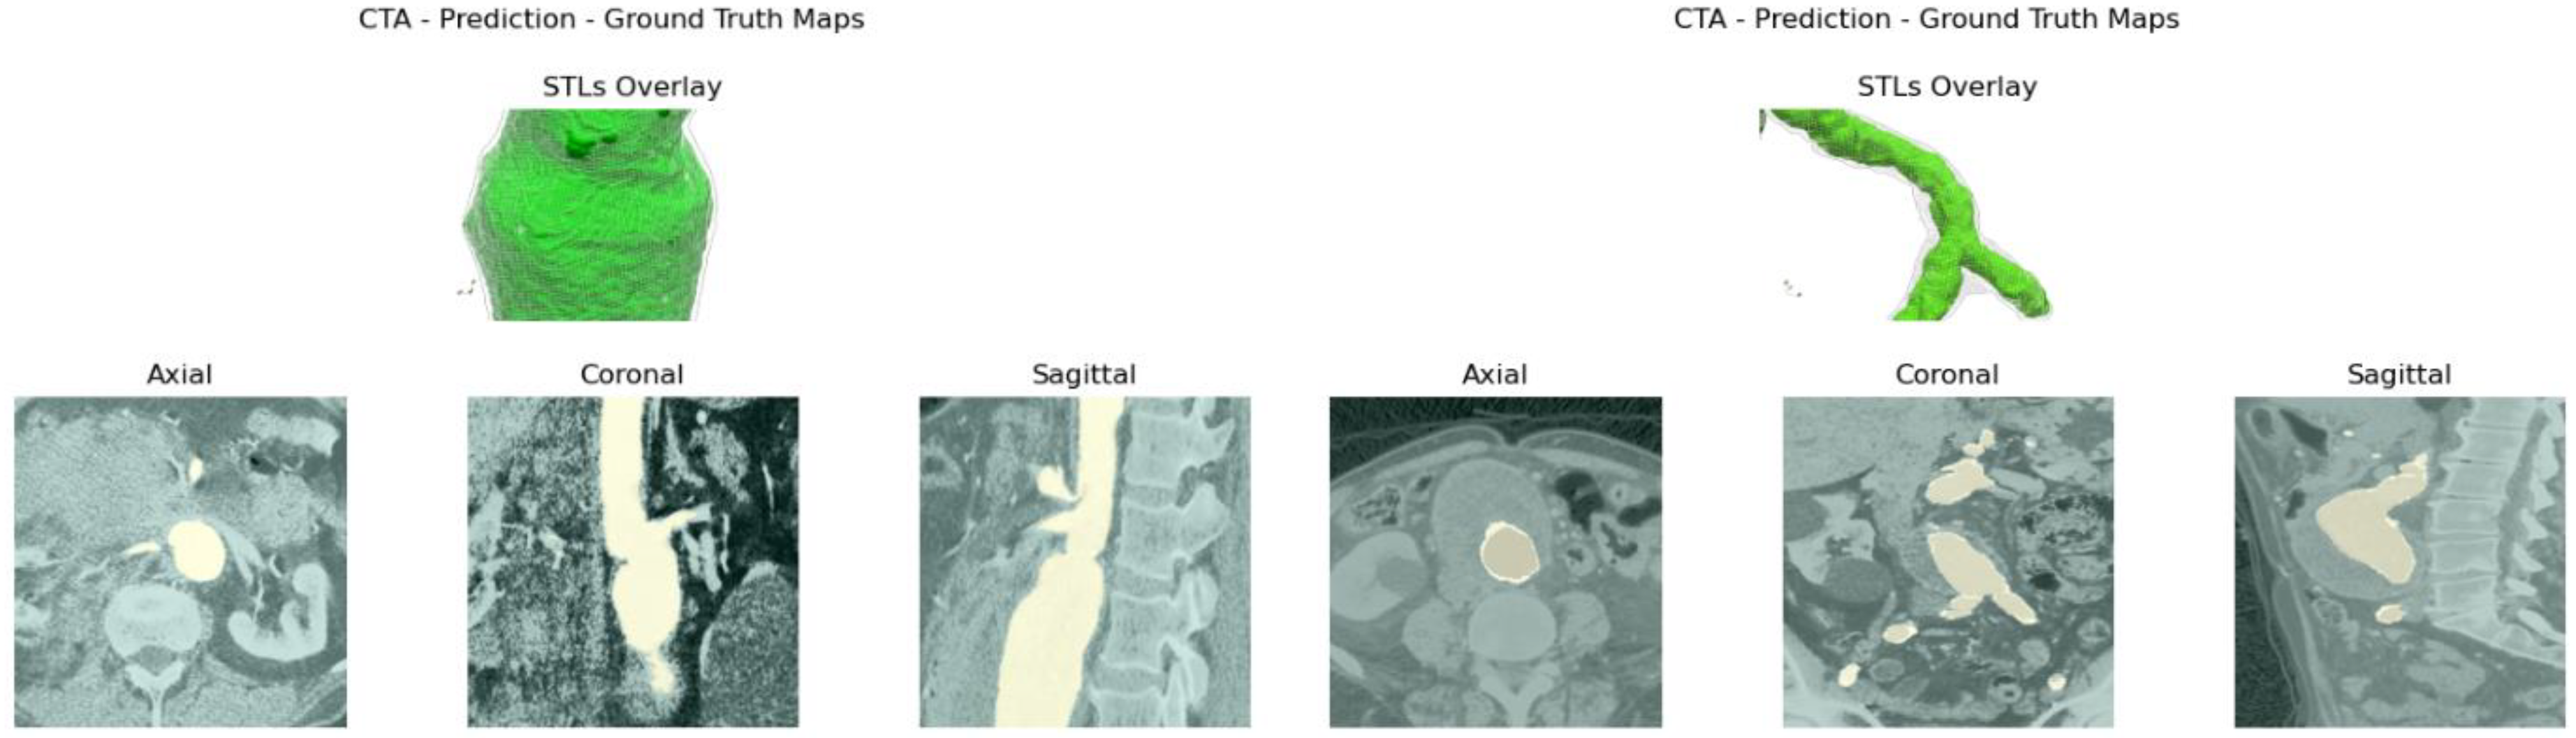

It is clear how, for cases ID_2, ID_4, ID_6, ID_11, ID_13 and ID_14, relative errors are characterized by higher values, especially for the common iliac arteries. Considering such sections, for instance in case ID_2, the underestimation of the aortic lumen by ITK-Snap segmentation leads to higher measurement relative errors, especially for diameters, which are lower in magnitude with respect to aortic lengths. To this purpose, a detailed view of the GT and prediction masks are reported in Figure 8.

From the axial, coronal, and sagittal view, the severe underestimation cited above can be seen. For the cases reported previously, the authors present the same detailed view from Figure A8, Figure A9, Figure A10 and Figure A11, qualitatively also clarifying how U-Net segmentations are more accurate when segmenting the aortic lumen. Such a phenomenon is due to the thresholding method used in ITK-Snap to segment the aortic lumen, which in most cases underestimates the lumen area. In fact, excessively lowering the lower threshold in ITK-Snap often expands the segmentation to other undesired areas and tissues. Hence, the very first layers of the aortic lumen are eroded from the GT mask. This leads to an underestimation of the aortic lumen and consequently higher error values.

Figure A8. Top: GT 3D reconstruction, in green, and U-Net 3D reconstruction wireframe (in white) overlay. Bottom: axial, coronal, and sagittal overlay of GT (in orange) and the difference between GT and U-Net predictions (in yellow) for case ID_11 (left) and case ID_13 (right).

Figure A9. Top: GT 3D reconstruction, in green, and U-Net 3D reconstruction wireframe (in white) overlay. Bottom: axial, coronal, and sagittal overlay of GT (in orange) and the difference between GT and U-Net predictions (in yellow) for case ID_6 (left) and case ID_12 (right).

Figure A10. Top: GT 3D reconstruction, in green, and U-Net 3D reconstruction wireframe (in white) overlay. Bottom: axial, coronal, and sagittal overlay of GT (in orange) and the difference between GT and U-Net predictions (in yellow) for case ID_4 (left) and case ID_2 (right).

Figure A11. Top: GT 3D reconstruction, in green, and U-Net 3D reconstruction wireframe (in white) overlay. Bottom: axial, coronal, and sagittal overlay of GT (in orange) and the difference between GT and U-Net predictions (in yellow) for case ID_14.